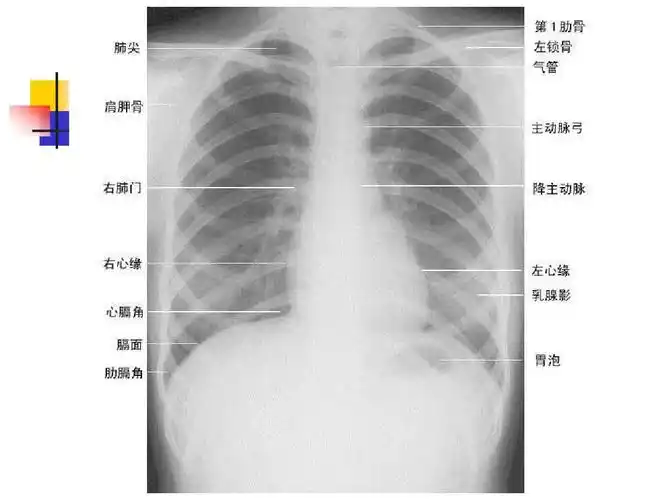

正常胸片胸部ct阅读